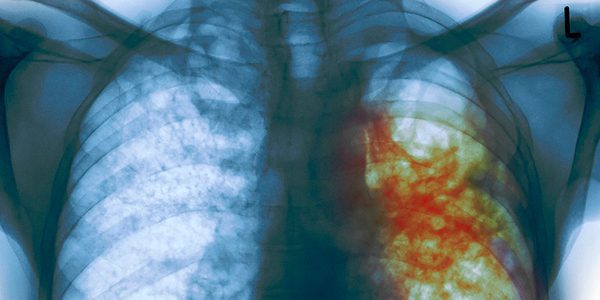

Вірус з Китаю живе поза тілом носія порівняно недовго, має відносно короткий «прихований» період і навряд чи так вже смертельний, якщо уважно подивитися на офіційну статистику. Інша справа – збудник туберкульозу – паличка Коха! У пилу під вашими ногами, там, де ви ведете за руку свою дитину, вона зберігається роками. І вдихнути її можна в будь-який момент. Повітря магазинів, шкіл та садочків береже її в собі приблизно півроку. Інкубаційний (прихований) період, коли хворий небезпечний для оточуючих, але ще не знає про це, може тривати до року. І обов’язкове обстеження на туберкульоз диво-лікарі визнали можливим замінити простим опитуванням. При цьому Запорізька область протягом декількох років очолює сумний рейтинг найбільшої кількості хворих на туберкульоз серед дитячого населення і впевнено підбирається до цього ж рекорду, але по населенню дорослому. До речі, така ж картина і по смертності, в тому числі дитячої. З того моменту, як 1 квітня закрили свої двері кілька протитуберкульозних диспансерів Запоріжжя і області, ймовірність зустріти хворого на відкриту форму для кожного з вас зросла в сотні разів. І це лише на той період, коли за своє існування продовжують боротися ще кілька установ в Запоріжжі, Мелітополі та Бердянську. Для них «час ікс» призначений на вересень. До речі, з 1995 року в Україні офіційно оголошено епідемію туберкульозу.

Лікарів-інфекціоністів влада «оцінила» тільки завдяки коронавірусу. Смертність від туберкульозу в багато разів перевищує смертність від ковіда (адже існує безліч стійких до антибіотиків, так званих мультирезистентних форм). Чи готове суспільство до нового карантину на пару-трійку років (адже прихований період набагато довше) або воно вимагатиме від влади нормального фінансування галузі – покаже час.